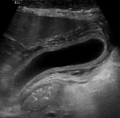

The hepatic fat calculator supports multiple imaging modalities to estimate liver fat fraction:

- Non-Contrast CT: Using liver attenuation values in Hounsfield Units (HU), the liver steatosis calculator estimates fat accumulation. Lower HU values or liver-to-spleen ratios can indicate higher hepatic fat fraction, providing a simple, non-invasive measure of steatosis.